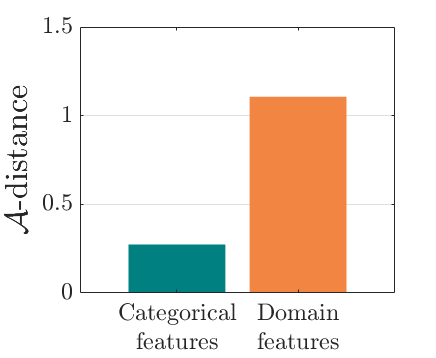

We adopt commonly-used statistical metrics, F1-score, recall and precision, to quantitatively evaluate classification performance. , and F1-score is the the harmonic mean of precision and recall. We report the average scores of these metrics for all examined methods. As suggested by [4], we utilize the -distance as a measure of domain divergence to quantitatively evaluate the separation of categorical and domain features. Similar to [19, 53], we train a SVM as a domain classifier to compute (the error of classifier) for the -distance, .

We compare the -distance of categorical features and domain features. Fig. 5 (a) shows that domain difference is higher in domain features than in categorical features. This indicates that domain features contain more domain information whereas categorical features are more domain-invariant. Fig. 6 shows the t-SNE plot of categorical features in both domains for MIDNet. From Fig. 6 (a), we observe that the categorical features learned by MIDNet enable the anatomical classification. Fig. 6 (b) shows that the learned categorical features are domain-invariant.

The experimental results of the state-of-the-art and the ablation study are shown in Table. II. In this table, we observe that the MIDNet model outperforms all the state-of-the-art methods on the most important test data for average F1-score, recall and precision. MIDNet+ performs better than MIDNet on and , demonstrating that metric learning is important and efficient for improving classification performance on images whose features have been observed during training. In the ablation study, MIDNet outperforms other variant models, especially MIDNet w/o , MIDNet w/o and MIDNet w/o , illustrating the effectiveness of all proposed components in MIDNet. In addition, Fig. 7 (a) shows that the -distance of MIDNet w/o is higher than that of MIDNet. This demonstrates that mutual information disentanglement () contributes to learn domain-invariant categorical features.